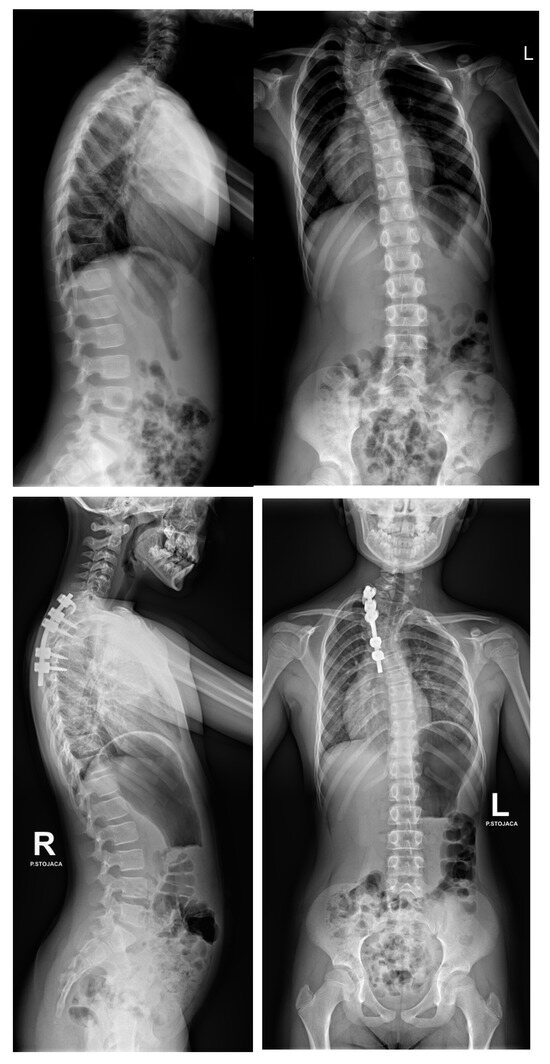

- Grabala, P.; Fani, N.; Gregorczyk, J.; Grabala, M. Posterior-only T11 vertebral column resection for pediatric congenital kyphosis surgical correction. Medicina 2024, 60, 897. [Google Scholar] [CrossRef] [PubMed]